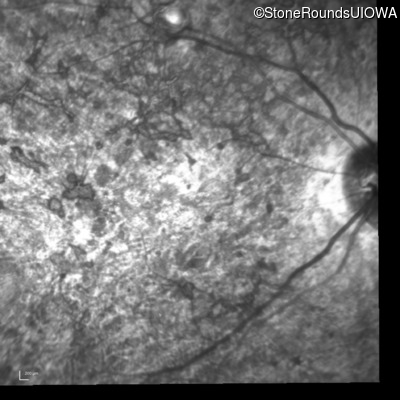

Infrared Fundus Photograph - Right - 20/400 sc

Exemplar